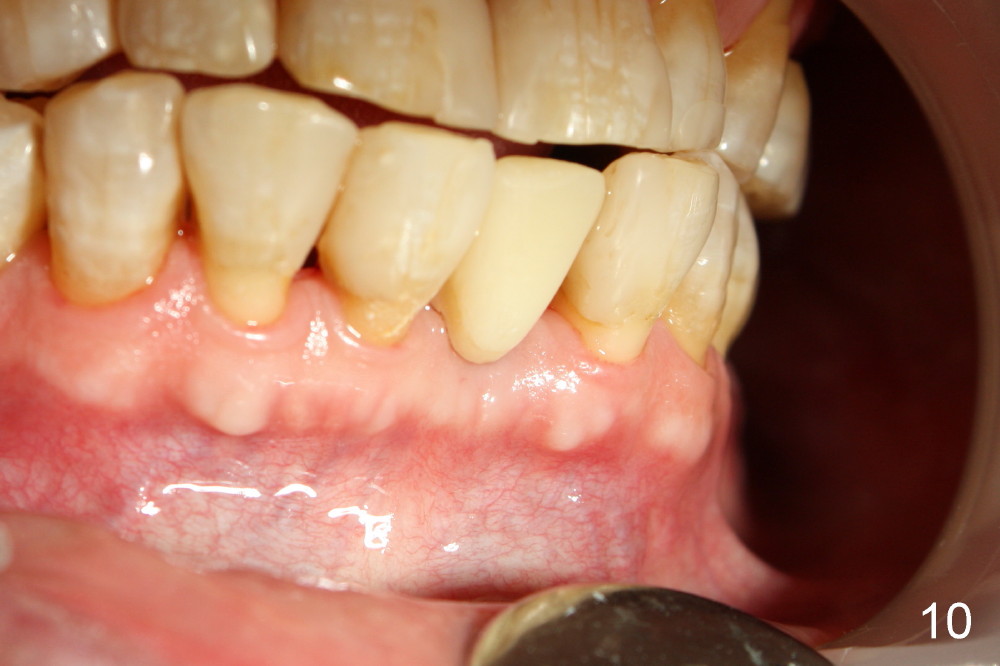

A 3x17 mm one piece implant is planned. Osteotomy is created by a 1.5 mm pilot drill at the depth of 14 mm without incision (Fig.2); it is close to a neighboring incisor. The trajectory of the osteotomy is intended to be changed (Fig.3 red) without success (white, 17 mm deep). With measurement and calculation, the 3x17 mm implant is not expected to touch the root of the adjoining tooth. In fact it is fine with insertion torque between 50-60 Ncm (Fig.4). Without incision, the papillae appear to form immediately following implantation (Fig.5). With adjustment of the abutment (Fig.6), an immediate provisional is fabricated (Fig.7).

Fig.10,11 show 7 day follow up. The permanent crown is seated 4.5 months postop (Fig.12). Minimal bone resorption occurs at the crest 4 months postop (Fig.13), which is most likely associated with conservative approach (flapless). The patient returns for follow up 2.5 months post cementation (Fig.14,15). The implant remains in the bone 4 years post cementation (Fig.16 CT coronal section; lingual thread exposure, corresponding to preop defect in Fig.1). There is mild coronal bone resorption 5 years 4 months post cementation (Fig.17).